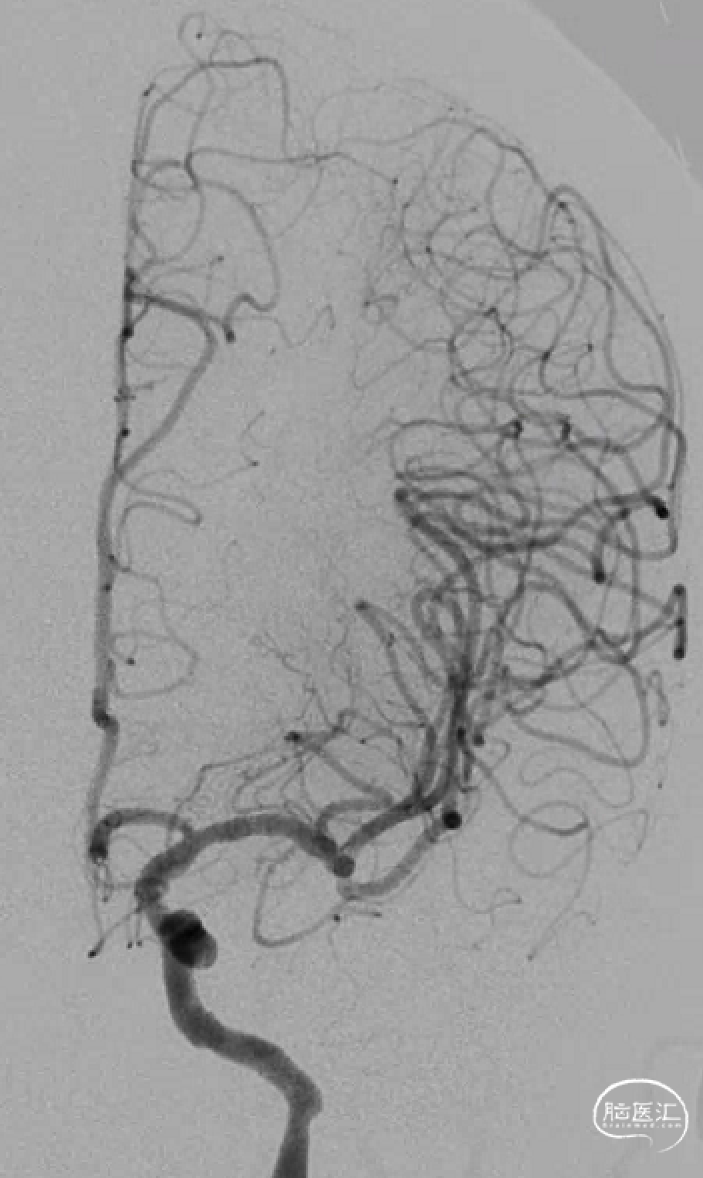

术前影像

脑血管造影(主动脉弓造影及后循环)

右侧颈动脉造影

左侧颈动脉造影

左侧颈内动脉重建(左侧狭窄及扩张较右侧更甚)